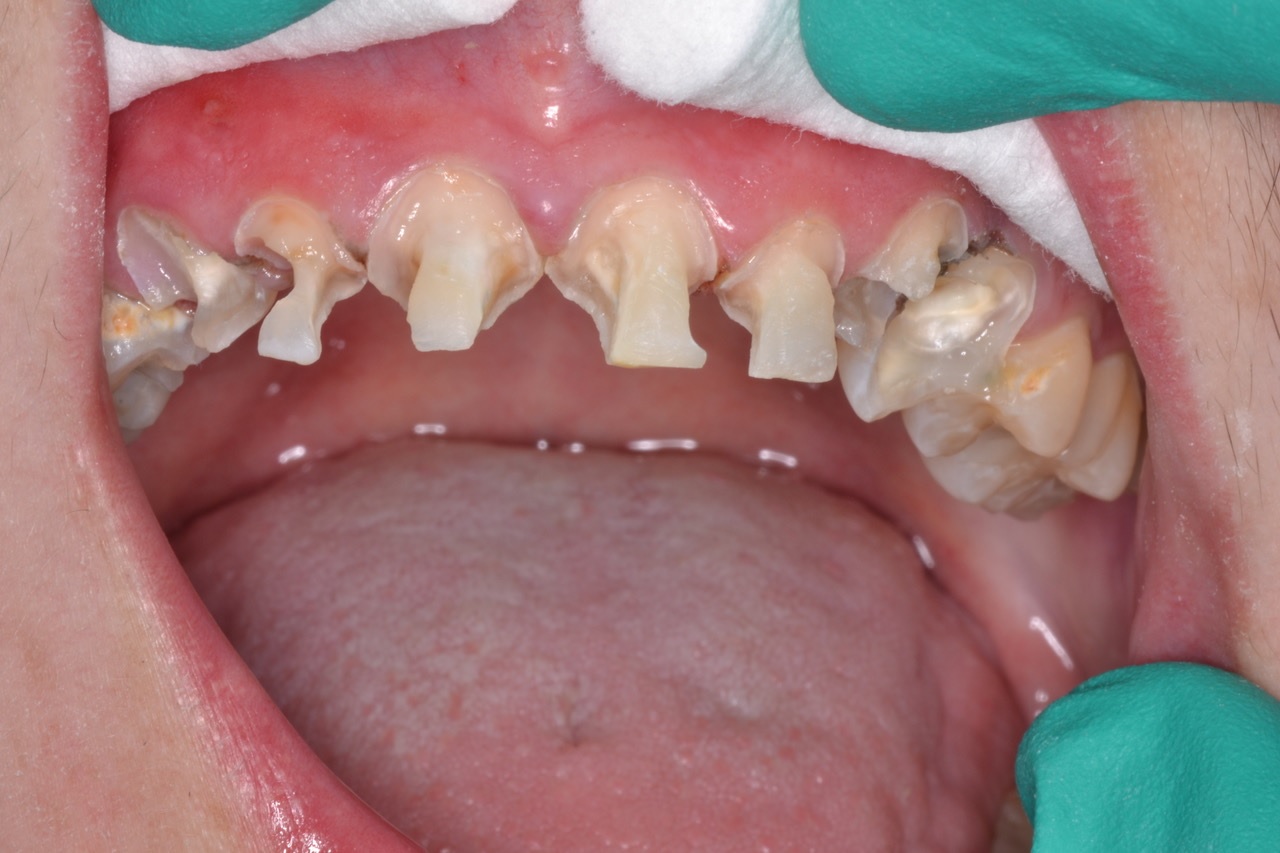

After removing the matrix, I easily removed excess with a scaler. Using serrated polishing strips, I separated each of the teeth proximally, and I made occlusal adjustments to achieve perfect contacts and anterior disclusion in all excursions. The case was completed in one long visit at a comfortable pace (Fig. 4).

Figure 4

Figure 4. Same day finished case immediately post-op